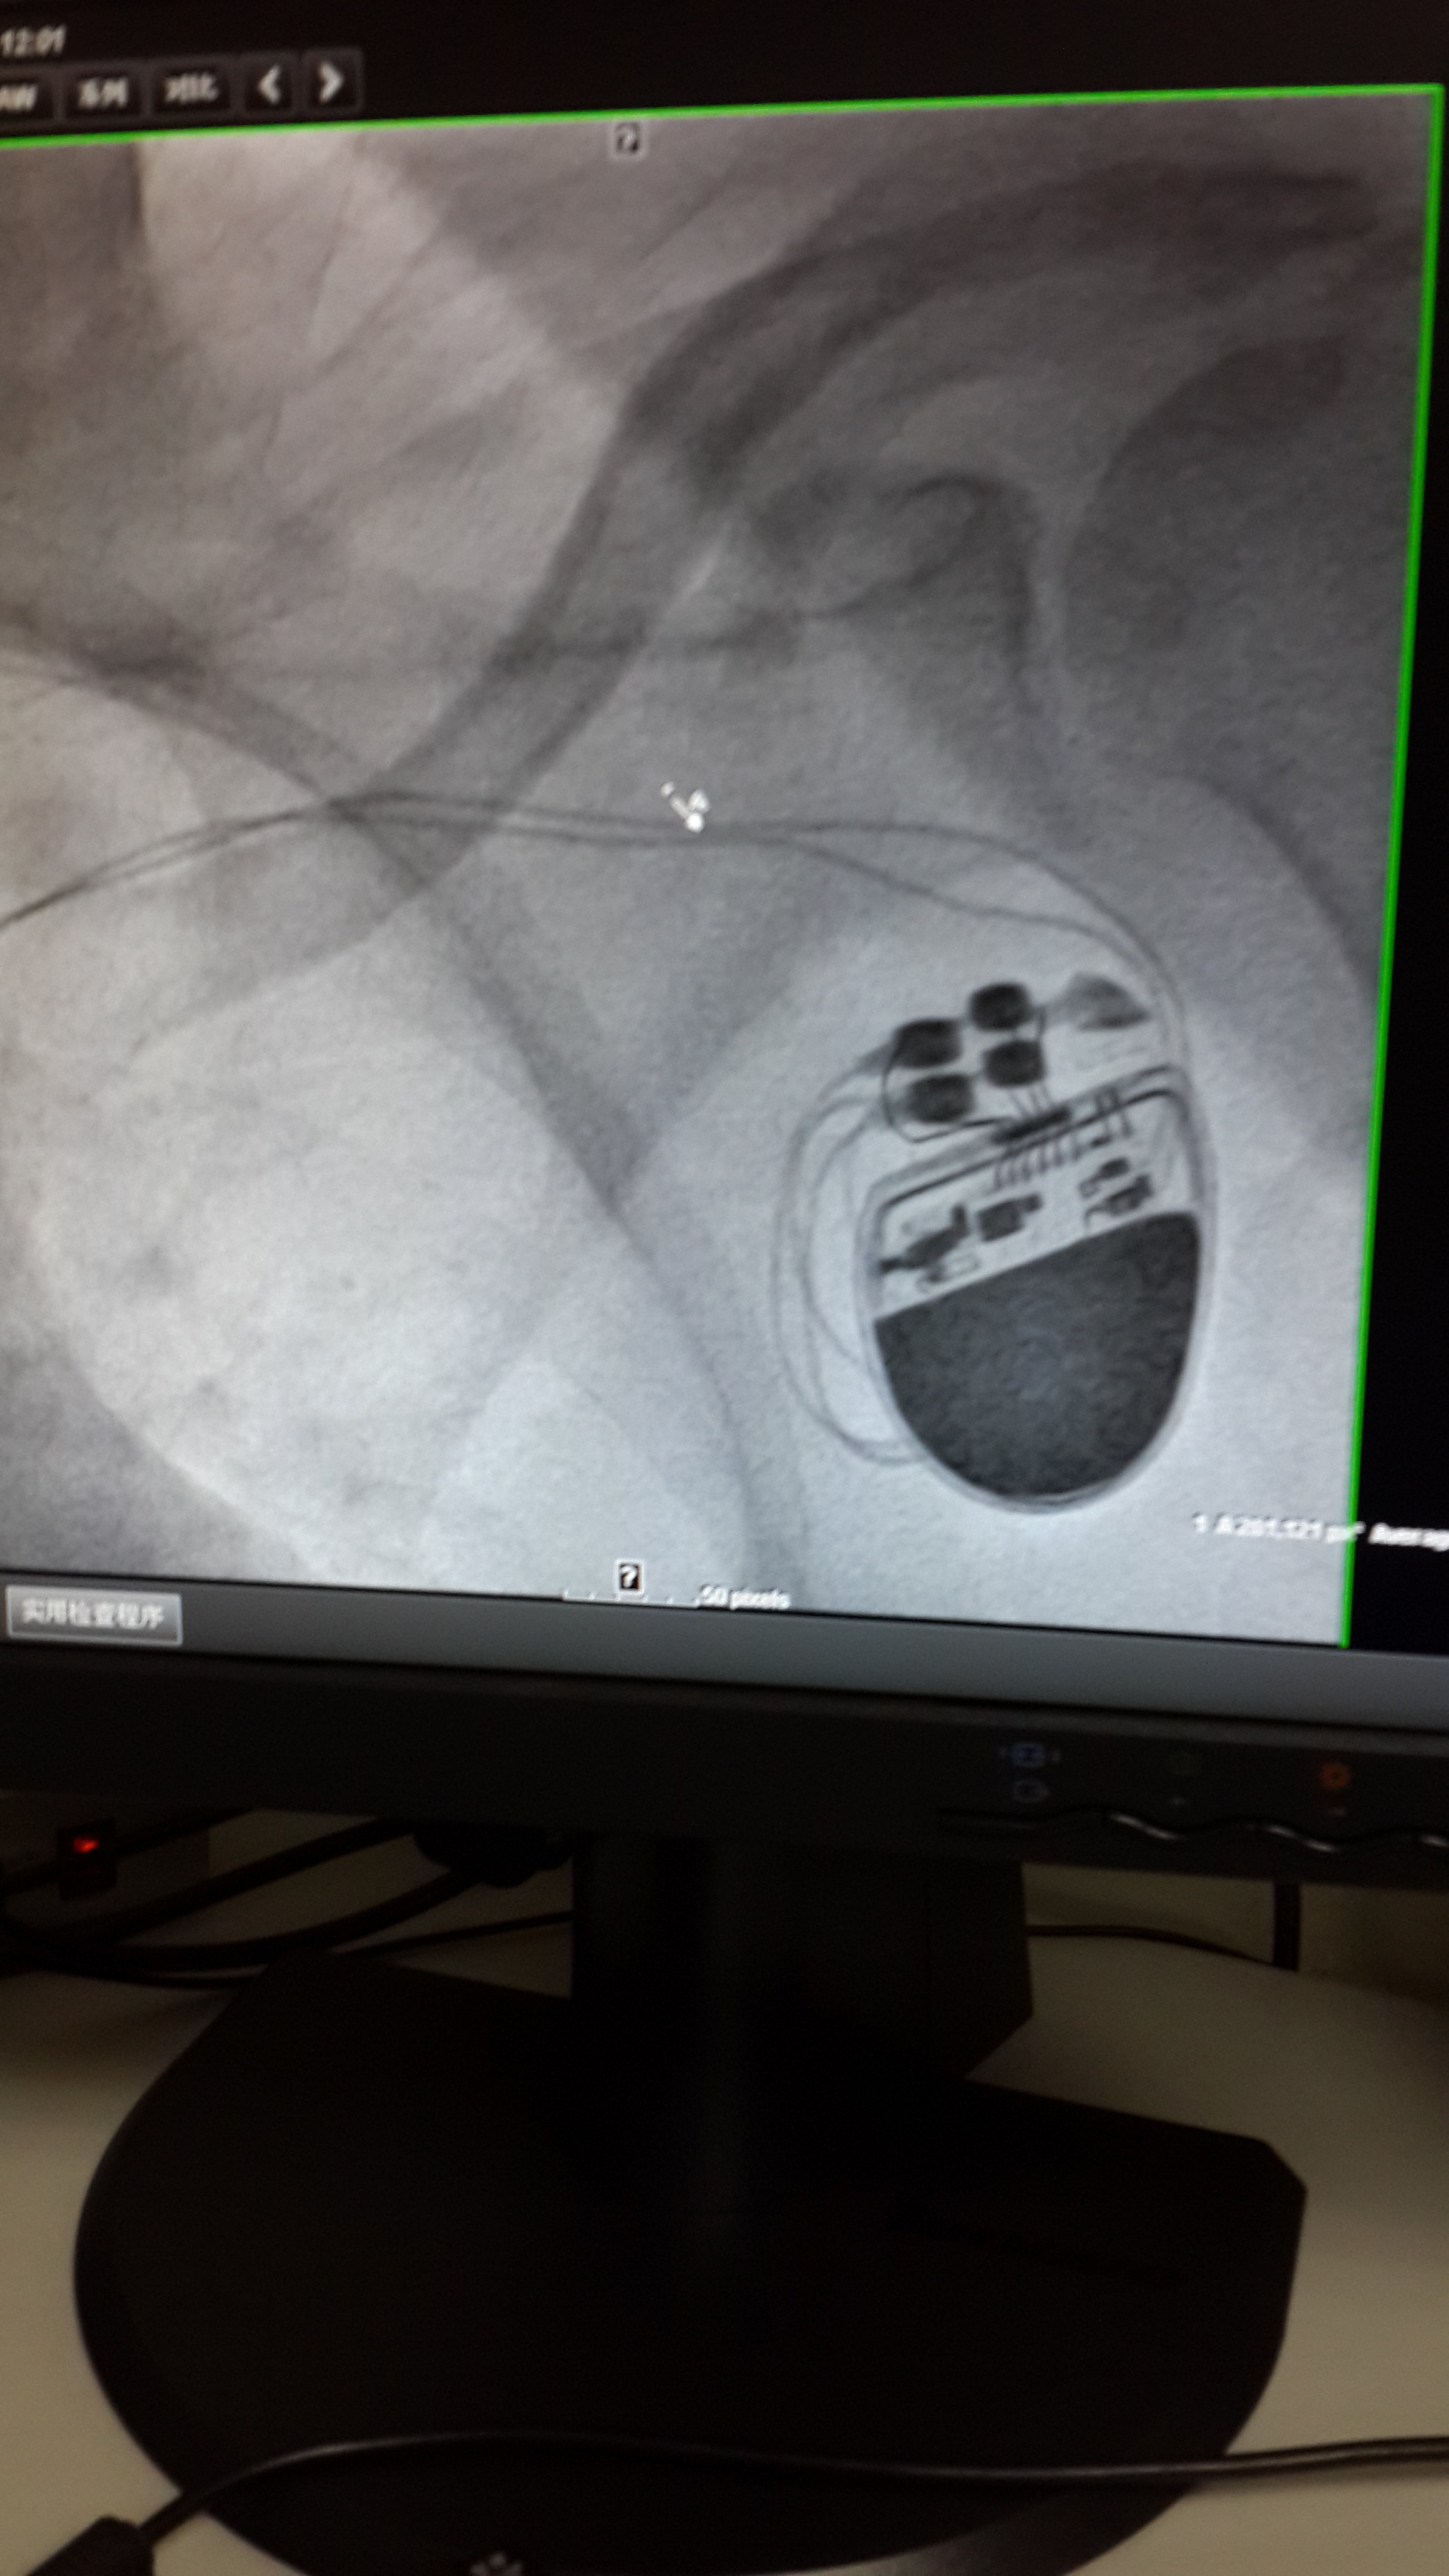

起搏器一治疗心动过缓利器

心动过缓